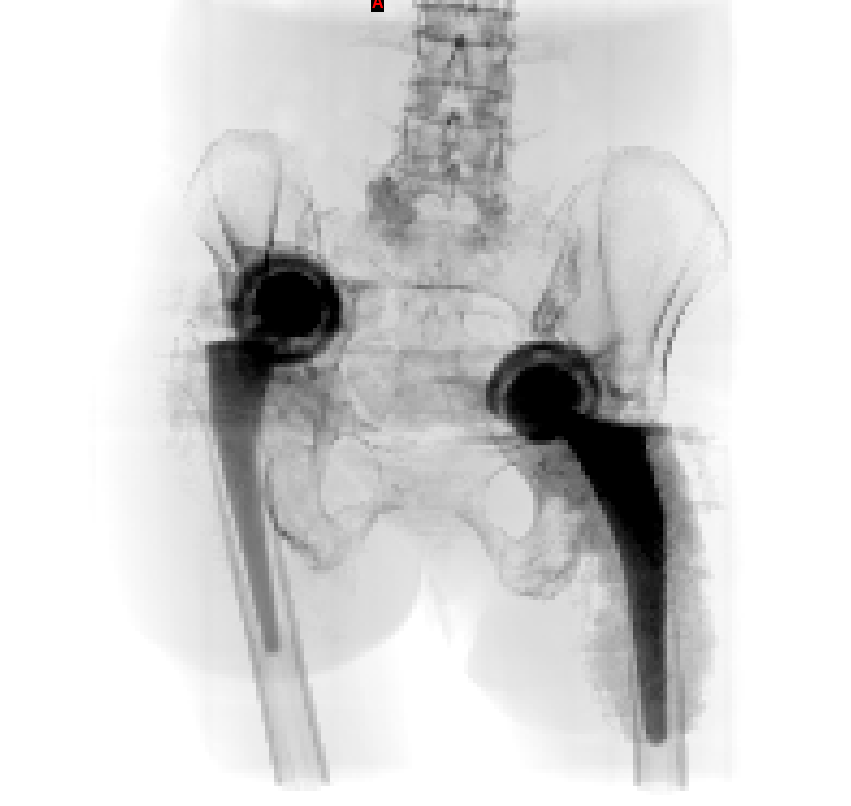

患者老年女性,类风湿性关节炎,骨质疏松,双侧全髋术后,髋臼假体移位至盆腔多年,不能行走。(The patient is an elderly female with rheumatoid arthritis and osteoporosis. After bilateral total hip surgery, the acetabular prosthesis has been displaced into the pelvic cavity for many years and she is unable to walk.)